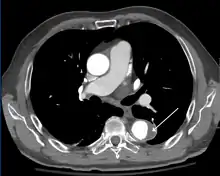

Computed tomography angiography is a fast, non-invasive test that gives an accurate three-dimensional view of the aorta. These images are produced by taking rapid, thin-cut slices of the chest and abdomen, and combining them in the computer to create cross-sectional slices. To delineate the aorta to the accuracy necessary to make the proper diagnosis, an iodinated contrast material is injected into a peripheral vein. Contrast is injected and the scan performed using a bolus tracking method. This type of scan is timed to injection to capture the contrast as it enters the aorta. The scan then follows the contrast as it flows through the vessel. It has a sensitivity of 96 to 100% and a specificity of 96 to 100%. Disadvantages include the need for iodinated contrast material and the inability to diagnose the site of the intimal tear.

CT with contrast demonstrating aneurysmal dilation and a dissection of the ascending aorta (type A Stanford)

Chest CT with descending (type B Stanford) aortic dissection (red circle)

Type A dissection with pericardial effusion as a result.